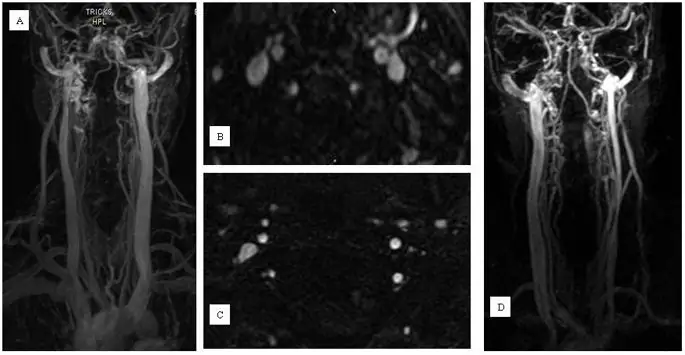

Техники с контрастным усилением

figure6

Пример морфологии нормального и аномального кровотока во внутренней яремной вене при магнитно-резонансной венографии. Морфология нормального (A и B) потока в обоих и аномального (C и D) потока в левой внутренней яремной вене при улучшенной трехмерной визуализации контрастной кинетики (TRICKS) с временным разрешением.

Наконец, MRV страдает от своего «снимка» природы. Точное изображение этих вен требует нескольких видов и маневров, таких как вдох и выдох, сгибание и разгибание, а также ротационная визуализация шеи. Его основными недостатками являются отсутствие динамичности MRV в реальном времени, более низкое разрешение по сравнению с DS и CV (невозможно оценить внутрипросветную патологию, такую как неподвижные клапаны, перепонки, перегородки, мембраны и дупликации), и это зависит от характера сами вены, которые склонны к разрушению в часто встречающихся условиях, в отличие от артерий. MRV часто обнаруживает ложные стенозы, которые не подтверждаются сердечно-сосудистыми заболеваниями, особенно в нижних отделах IJV (42, 123). Эти стенозы могут представлять собой преходящие фазовые сужения (функциональные) или могут быть результатом уменьшения потока над истинными стенозами, обычно расположенными в месте слияния вен (30, 31, 102, 123). Кроме того, он не может удовлетворительно оценить азиготные и гемиазиготные вены.

В отличие от DS, с большинством МР-сканеров данные можно собирать только в положении лежа на спине, хотя некоторые сканеры также могут выполнять сканирование в вертикальном положении. Ниггеман и соавт. использовали позиционную МРТ для описания влияния позиционных изменений на венозный отток головного мозга (129). Они обнаружили, что стриктуры IJV являются обычным явлением для здоровых людей в положении лежа на спине, не имеющих значения в вертикальном положении, что ставит под сомнение обоснованность критерия DS VH 5 (отсутствие коллапса IJV в вертикальном положении) для диагностики CCSVI. Очевидно, что этот критерий (для изучения изменения потока в IJVs от положения лежа на спине до положения сидя) не может быть изучен с обычной системой MR (130).